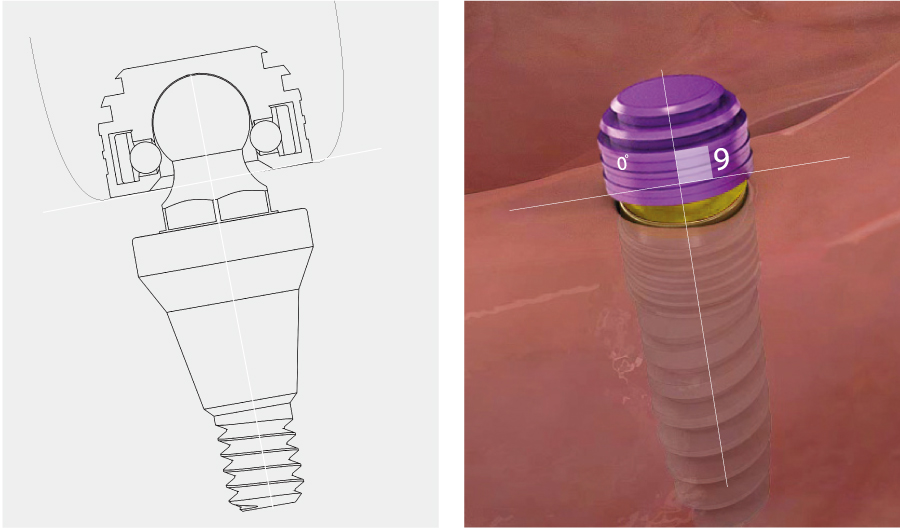

부분 상세설명 소모품교체 없음

소모품교체 없음Titanium housing과 Zirconia ball, Nitinol pan spring으로 이루어져 있어 소모품 교체 없이 장기간 사용이 가능하다.

Fixture 보호Locking 시 지대주와 housing 사이에 0.8mm 가량의 공간이 부여되어 의치 기능 시 연조직의 위축량을 보상함으로써 지대주에 가해지는 힘을 줄일 수 있다.

편측 20도 각도 보상

편측 20도 각도 보상지대주의 groove와 housing ball & spring이 체결되는 ‘EZ LOCKING 방식’에 의해 fixture의 식립각도를 20도까지 보상할 수 있다. (각도별 housing positioner 이용)